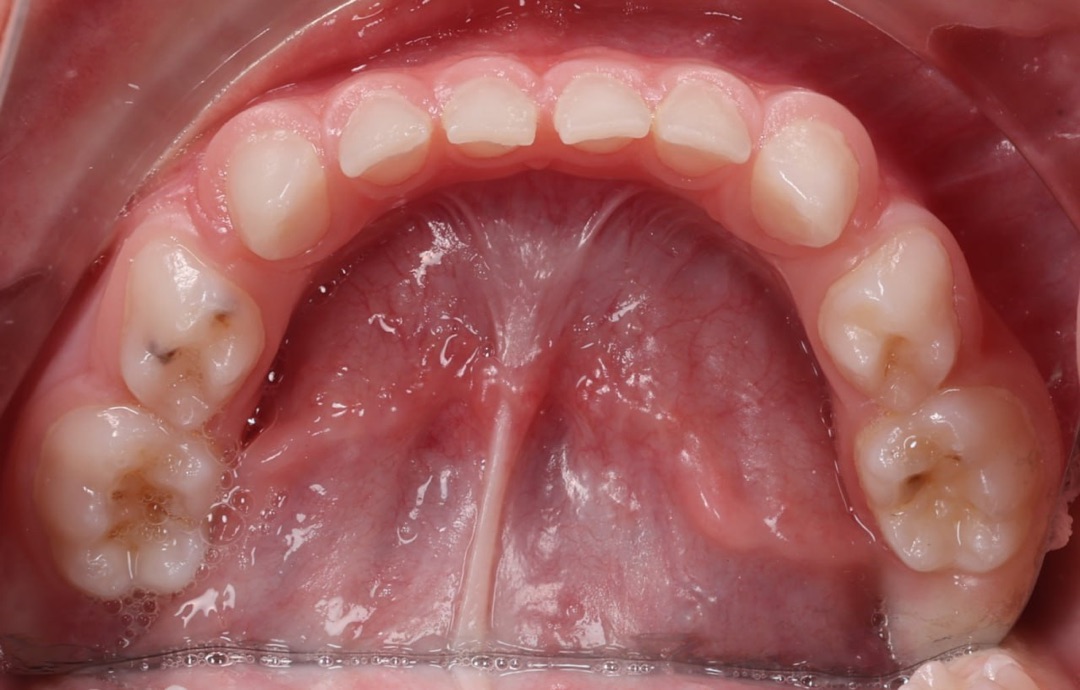

Дитина звернулася до нашої клініки разом із батьками зі скаргами на неправильний прикус. Під час первинного огляду було встановлено, що для досягнення правильного змикання зубів необхідно розпочати лікування з підготовчого етапу.

На представленому фото — результат після першого етапу лікування, на якому вже помітні позитивні зміни прикусу.

Як проходив перший етап лікування

На першому етапі було виконано розширення верхньої щелепи. Для цього дитині встановили незнімний розширювальний апарат на верхню щелепу, який дозволяє:

• створити достатній простір для правильного розташування зубів;

• покращити співвідношення щелеп;

• підготувати зубощелепну систему до наступних етапів ортодонтичного лікування.

Вже після завершення цього етапу прикус почав змінюватися, що є важливим показником ефективності лікування.

Поточний стан і подальший план

На даний момент дитина носить лицьову маску, яка допомагає скоригувати ріст щелеп і закріпити отриманий результат. Після завершення цього етапу планується подальше лікування з використанням брекет-системи для точного вирівнювання зубів і стабілізації прикусу.

Ортодонтичне лікування у дітей часто проходить поетапно, і саме ранній початок дозволяє досягти більш прогнозованого та стабільного результату в майбутньому.